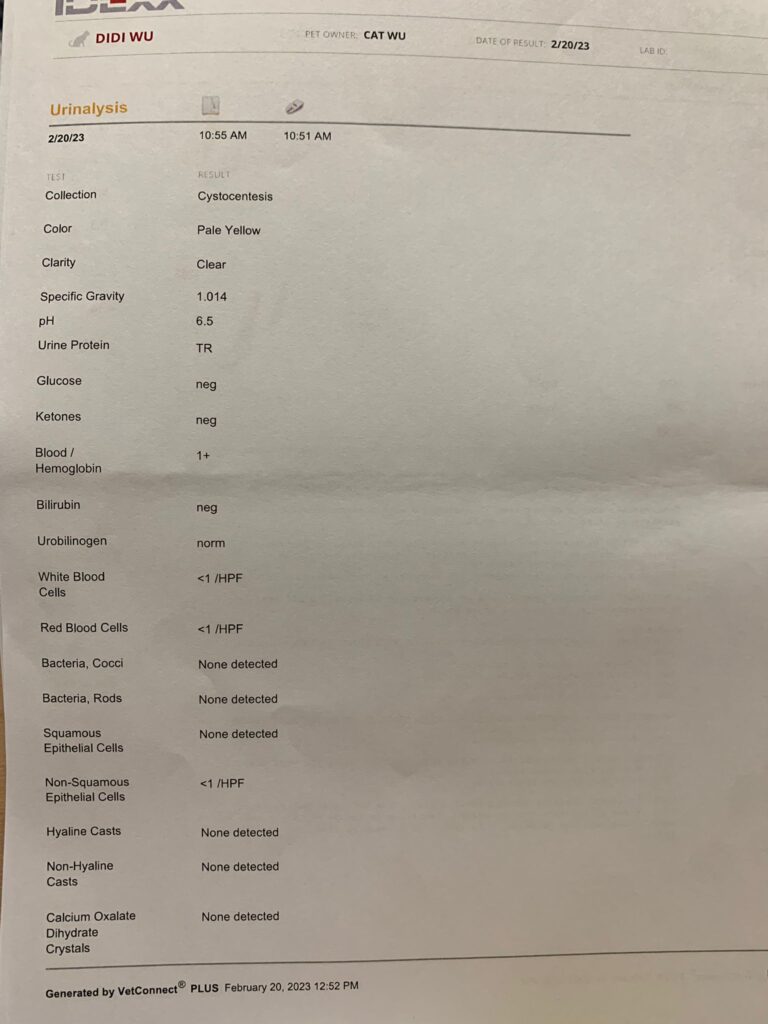

20 Feb 2023

Sg 1.014 – Dilute urine, losing a little protein in urine, can try low dose semintra 1mg/kg (nowadays vet give 2mg per kg, n they finally acknowledge that 10-15% become anemic as a side effect)

I trying 0.5mg/ kg and review to make sure rbc stable n upc go down. UPC 0.39

Rbc down to 6.12, lucky HCT still 30.3%.

Wbc NEU all go up.

He poo 1.5/10, w blood (dr d says may be due to stress)